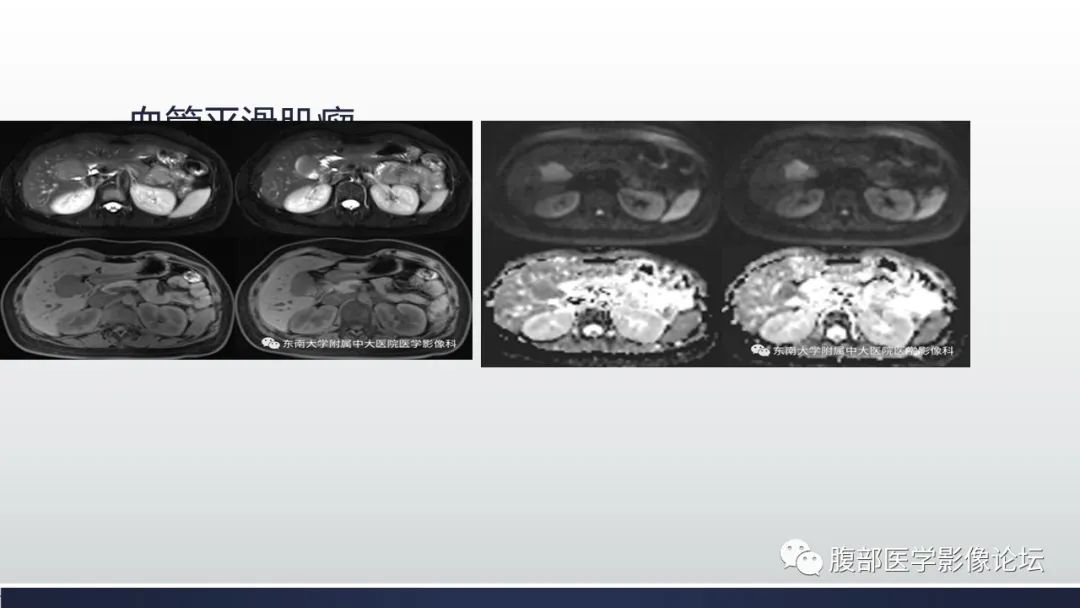

【病例】胆囊管状腺瘤1例CT及MR影像表现-2